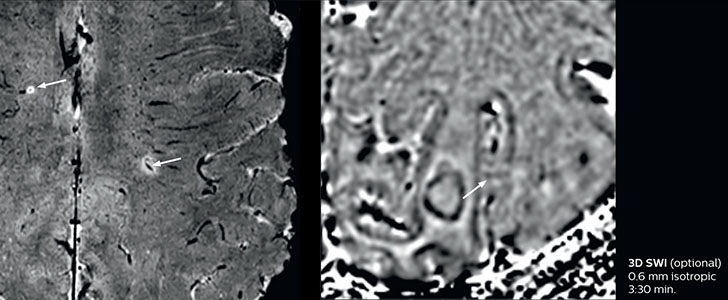

Giant cell arteritis

The 3D TSE T1w black blood MSDE sequence with fat suppression has an isotropic 0.8 mm voxel size and sagittal oblique and axial reformats are made. The images show superficial temporal artery thickening and peri-arterial fat infiltration. The 3D TSE PDw black blood MSDE with fat suppression has 0.55 mm isotropic voxels. The images shows focal involvement of the frontal branch of the superficial temporal artery.

3D TSE T1w BB MSDE

3D TSE PDw BB MSDE